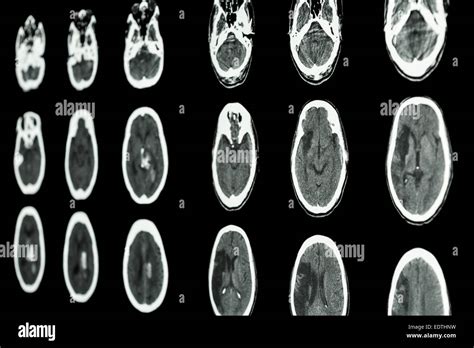

Before we jump into the details of the CT scan , let’s get on the same page about ischemic strokes. An ischemic stroke happens when the blood supply to the brain is cut off, usually because of a blood clot. This blockage starves the brain of oxygen and nutrients, leading to brain cell damage, and, if not treated quickly, this can result in permanent brain damage. Now, think of the brain as a complex network of highways and roads. The blood vessels are the highways delivering all the essential supplies, and if a roadblock (a clot) forms, traffic (blood flow) stops. The result? A stroke. Getting a quick diagnosis is super important. That’s where the CT scan comes into play. A CT scan, or computed tomography scan, is a type of imaging technique that uses X-rays to create detailed pictures of the inside of your body. Imagine taking a series of X-ray pictures from all angles, and then the computer puts them together to create a comprehensive, cross-sectional image. For the brain, this means doctors can see the structures in great detail, look for bleeding, and, most importantly, identify signs of an ischemic stroke .

Okay, so why is a CT scan so crucial? Well, when someone shows stroke symptoms (like sudden weakness, trouble speaking, or vision problems), doctors need to figure out what’s going on fast . The faster they can determine the cause of the stroke, the faster they can start treatment. A CT scan is often the first imaging test done because it’s quick, readily available in most hospitals, and can quickly rule out other possible causes of the symptoms. For instance, it can differentiate between an ischemic stroke and a hemorrhagic stroke (which is caused by bleeding in the brain), which is super important because the treatments are very different. In an ischemic stroke , the CT scan might show early signs of damage, such as subtle changes in the brain tissue, or it might reveal the absence of blood flow to certain areas. These early indications help doctors decide the best course of action. It can also help see if there’s any bleeding. It might not always show the stroke immediately, especially in the early hours. However, it’s still extremely valuable for ruling out other conditions and for helping doctors make a quick assessment.

Let’s break down how a CT scan works so you know exactly what’s happening during the process. When you get a CT scan, you’ll lie on a table that slides into a doughnut-shaped machine. Inside the machine, an X-ray tube rotates around your head, taking multiple images. These images are then processed by a computer, which puts them together to create detailed, cross-sectional pictures of your brain. The whole process is pretty quick, usually taking only a few minutes. You might be asked to hold still and, in some cases, you might receive an injection of a contrast dye. This dye helps to highlight the blood vessels and other structures in the brain, making it easier to see what’s going on. The images produced by a CT scan are incredibly detailed. They allow doctors to see different densities of tissues, like the brain, blood vessels, and any potential abnormalities such as clots, bleeding, or swelling.

In the early stages of an ischemic stroke , the CT scan might not show a lot of obvious changes. However, there are some subtle signs that experienced radiologists can spot. They look for the following signs:

• Loss of Grey-White Matter Differentiation: The brain is made up of grey matter and white matter, which have different densities. In the early stages of a stroke, the difference between these can become less clear, making it difficult to differentiate between them. This is often the first thing they notice.

• Hyperdense Artery Sign: Sometimes, the CT scan can show a blood clot as a very bright spot in an artery, known as the hyperdense artery sign. This is a telltale sign of a blood clot and helps to confirm the diagnosis.

• Subtle Swelling: The brain tissue may start to swell, and subtle changes in the density of the brain tissue. This can indicate that the brain is not getting enough blood.

Later Signs of Ischemic Stroke on a CT Scan

As time passes, the changes on the CT scan become more apparent. The following signs are usually visible later:

• Hypodensity: Areas of the brain that are damaged due to the lack of blood flow will start to appear darker on the CT scan. This is called hypodensity. It indicates that the brain tissue is dying.

• Mass Effect: As the brain swells, it can push on other structures, causing a mass effect.

• Infarct: This is a term for the area of dead tissue caused by the stroke. It can be seen as a clearly defined dark area on the scan.

Differentiating Ischemic vs. Hemorrhagic Stroke

One of the main goals of the CT scan is to differentiate between an ischemic stroke and a hemorrhagic stroke. A hemorrhagic stroke involves bleeding in the brain. On a CT scan, blood appears bright white. So, if the scan shows any bright white areas, it’s a sign of bleeding. If there’s no bleeding and the scan looks relatively normal (or shows the signs of ischemic stroke ), then it’s most likely an ischemic stroke . This distinction is super important because the treatments for each type of stroke are different.